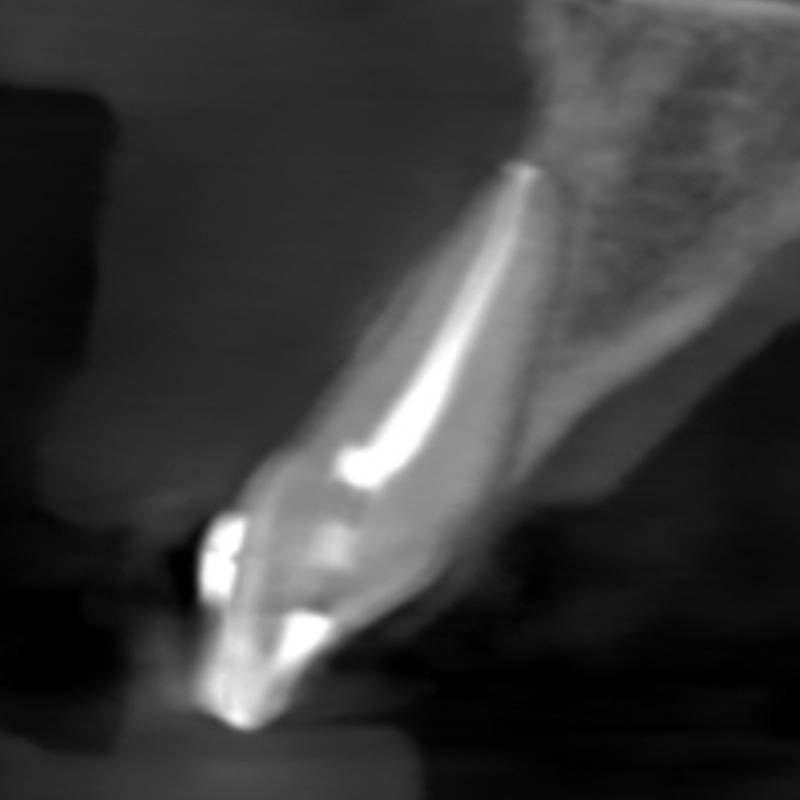

Resorption

Resorption is a condition where the tooth’s structure starts to break down, either from the inside out or from the outside in. It can be caused by trauma, inflammation, or other factors. Endodontic treatment for resorption involves removing the damaged tissue and reinforcing the tooth with materials that help prevent further damage. The aim is to save the tooth and maintain its functionality as much as possible.